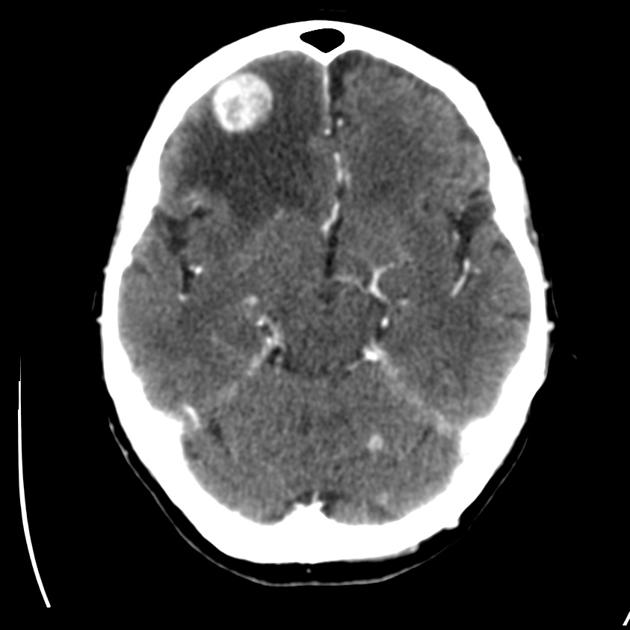

- There is a right, anteriorly located, frontal lobe lesion, hyperdense as compared to the brain parenchyma. Moreover, there is surrounding oedema. The mass also shows specks of hypodensity, which are indicative of chronic bleeding;

- The brain herniates downwards due to the mass effect of the lesion, compressing against the brainstem and cerebellum.

CT Brain (with contrast added) showing a contrast-enhanced, hyperdense, singular lesion over the right frontal lobe, with surrounding oedema (hypodense to the brain parenchyma). The scan is extracted from: https://s3.amazonaws.com/static.wd7.us/8/89/CT_scan_of_brain_metastasis_12.jpg.